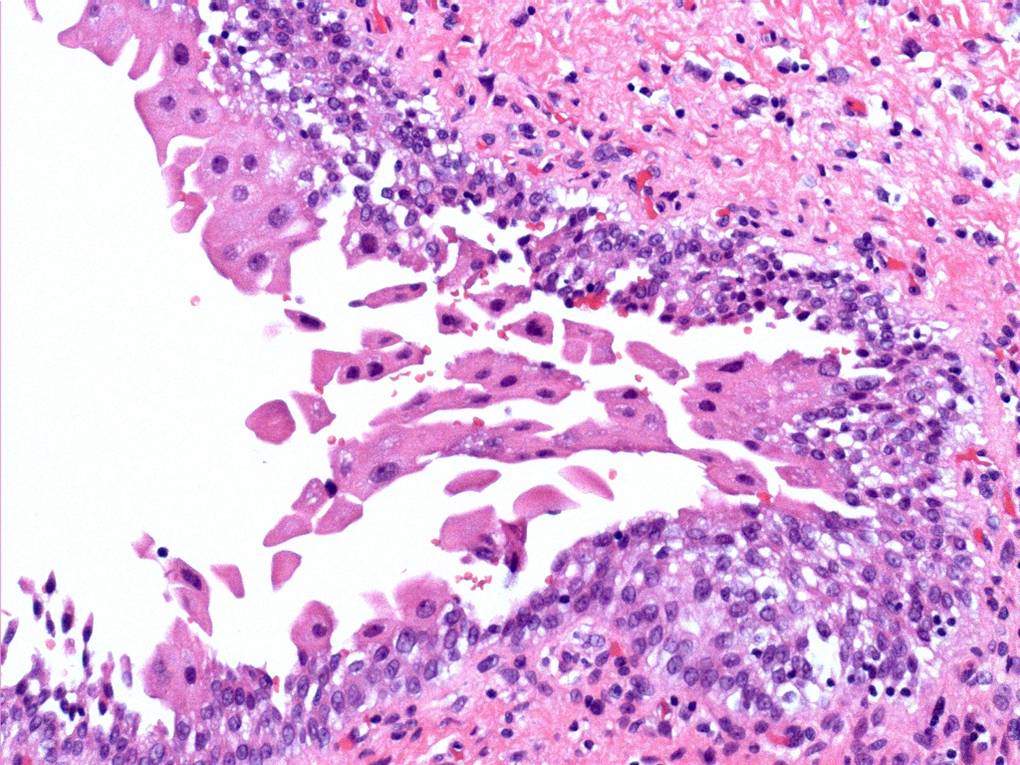

Consensus grade: Reactive atypia

Case description (by case creator):

The main change here is ‘degenerative’ nuclear atypia in a rather unusually prominent umbrella cell layer. The underlying urothelium shows mild reactive changes in places with some chronic inflammation in the lamina propria.